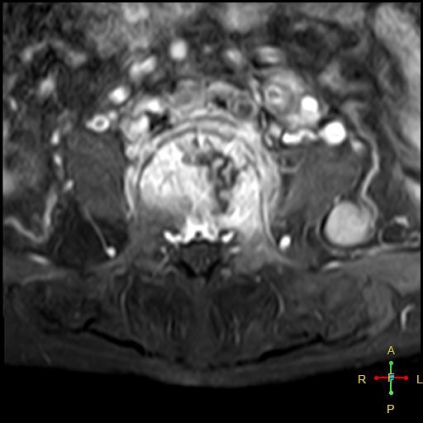

3 恶性压缩性骨折 椎体上下径变窄而前后径增大,椎体后部皮质后突,后角一般表现圆钝,无上翘,常呈球形突出,致椎管狭窄,即膨胀性盘状破坏,硬膜囊和脊髓受压。

——恶性压缩性骨折MR信号特点—— 由于肿瘤组织的侵犯,T1WI上椎体呈弥漫性低信号,T2WI呈高信号,增强扫描呈明显不均匀强化。

转移瘤 椎弓根改变:椎弓根膨大仅见于恶性压缩性骨折,故为其特异性,可作为鉴别诊断的依据。

椎旁软组织肿块:在转移瘤中,受累椎体周围多出现分叶状或肿瘤样软组织肿块,此征象仅见于恶性压缩性骨折。故,椎旁薄环状软组织与瘤样软组织肿块是鉴别骨折性质较有特征性的征象。